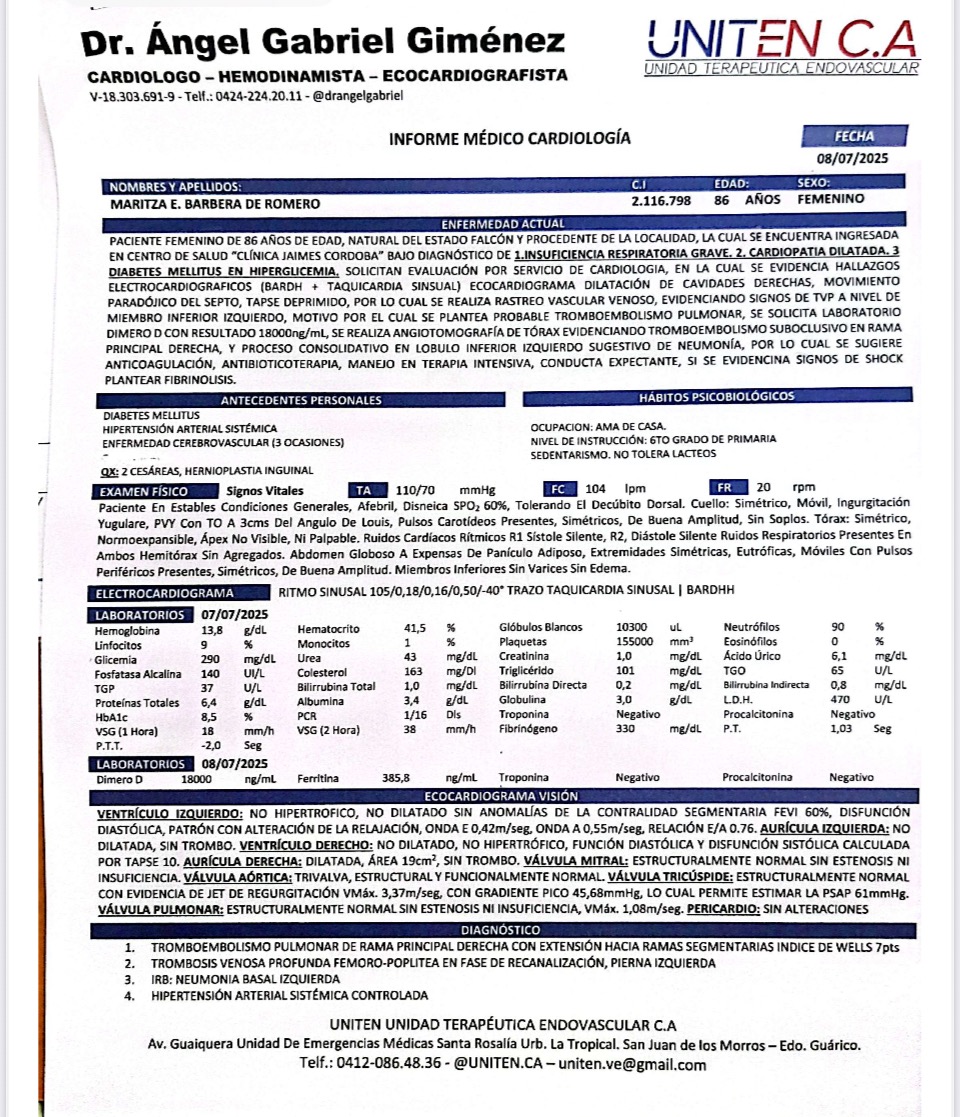

1.-Tromboembolismo Pulmonar de Rama Principal Derecha con Extensión hacia Ramas

Segmentarias

2.-Trombosis Venosa Profunda Femoro-Poplitea Pierna Izquierda en Fase de

Recanalización.

3.-Neumonia Basal Izquierda